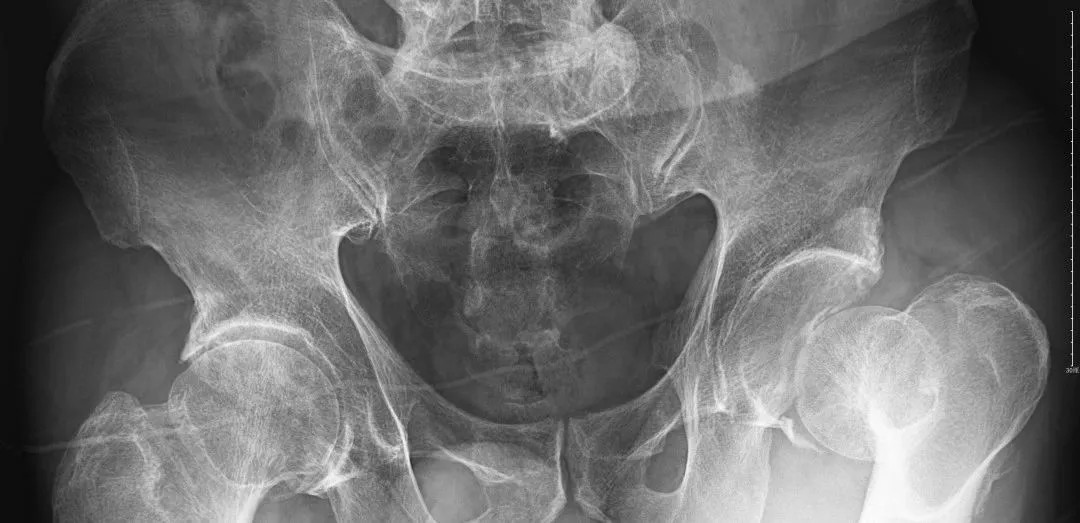

經(jīng)過王副主任認(rèn)真仔細(xì)的檢查,并結(jié)合X線攝片后,他告訴患者及其家屬:“周大爺是外傷導(dǎo)致的急性髖關(guān)節(jié)脫位、髖臼骨折!”一聽脫位骨折了,患者及家屬焦慮萬分,擔(dān)心手術(shù)給身體和經(jīng)濟(jì)帶來的巨大壓力。王副主任耐心告知周大爺一家人:“周大爺這種病情可以保守治療,用我們顧氏的正骨手法可以復(fù)位的,不需要開刀,價格也實(shí)惠”。家屬聽到不用做手術(shù),瞬間放心不少,表示非常愿意配合治療。

(術(shù)后復(fù)片  關(guān)節(jié)對位良好)